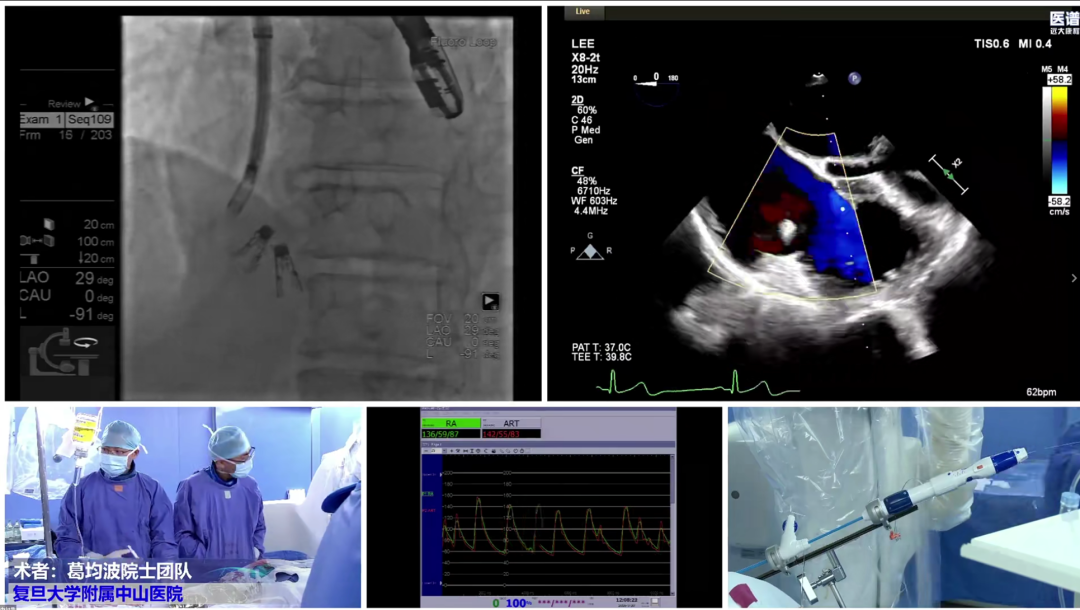

Subsequently, the Fudan Zhongshan Cardiac Team delivered the first LIVE surgical demonstration of the day, fully presenting the entire procedural workflow of transcatheter tricuspid annuloplasty. From preoperative patient evaluation and the surgical procedure to immediate postoperative outcome verification, team experts provided synchronized real-time commentary, clearly breaking down each operational step. This allowed attending physicians to immerse themselves in the precision and standardization of high-level interventional surgery.

Immediately afterwards, the Fudan Zhongshan Cardiac Team delivered the second LIVE surgical demonstration. Jointly with a multidisciplinary team including ultrasound, interventional cardiology and anesthesiology, they fully presented the entire interventional treatment process for a patient with complex tricuspid regurgitation, intuitively demonstrating the important value of multidisciplinary collaboration in valvular interventional diagnosis and treatment.